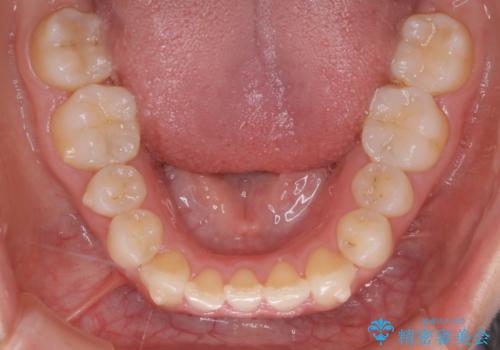

下顎については、前歯にがたつきがありました。

下顎については、歯の側面を削ることをメインにがたつきを改善しました。